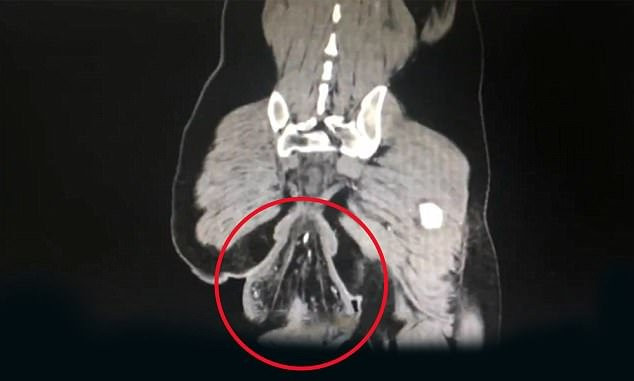

Hình ảnh X-quang chụp bướu lạ rơi ra khỏi cơ thể người bệnh.

Sự việc xảy ra ở Zhongshan, Quảng Đông ngày 4/2 khi một người đàn ông phải đến bệnh viện vì phát hiện một cục bướu rơi ra ngoài cơ thể, với đường kính 16 cm. Bác sỹ sau đó cho biết cục bướu này là trực tràng của bệnh nhân, bị mất kết nối với cơ thể nên rơi ra.

Bác sỹ cho biết thêm, một trong những nguyên nhân có thể gây ra hiện tượng này là vì người đàn ông ngồi trong toilet hơn 30 phút. Anh ta được chẩn đoán bị chấn thương trực tràng, khiến phần cuối cùng của hệ thống tiêu hóa mất kết nối với cơ thể và rơi ra ngoài.